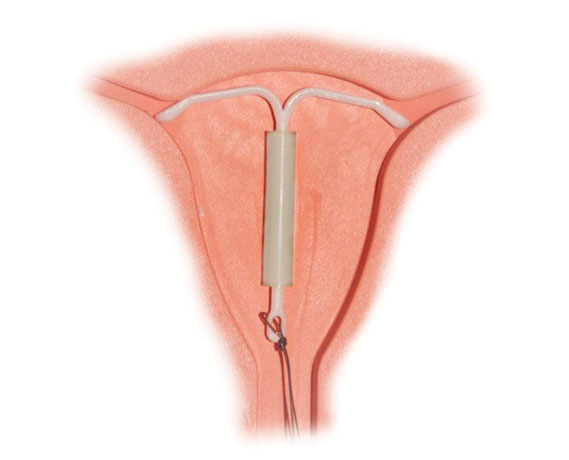

Myomların klinik bulguları genellikle lokalizasyonları ile ilişkilidir. Rahim kavitesinin içine doğru büyüyen submüköz myomlar, uzamış ve ağır kanamaya neden olurlar. Bu myomlar aynı zamanda gebe kalmak isteyen kadınlarda da problem yaratırlar. Subseröz myomlar ise rahimin dış kısmına doğru büyüyen myomlardır. Bazen mesaneye bası yaparak idrar ile ilgili şikayetlere neden olabilirler. Eğer rahmin arka tarafına doğru büyürlerse rektuma bası ile kabızlık, spinal sinirlere bası ile bel ağrısına neden olabilirler.

Myomlar, genellikle gebe kalmaya engel olmasalar bile yerleşim yerlerine bağlı olarak spermlerin rahim içine girişlerine ya da tüplerden geçişine engel olabilirler. Yine rahim iç tabakasına yerleşmiş olan myomlar embriyo gelişimini engelleyebilirler. Gebelikte ise myomlar sıklıkla karın ve kasık ağrısı şikayetine neden olurlar. Bazı nadir durumlarda ise düşük ya da erken doğuma sebebiyet verebilirler.

Myomlar, genellikle tedavi gerektirmezler fakat hastada aşırı kanama, anemi, ağrı ya da gebeliğe engel durum oluşturuyorlarsa cerrahi olarak çıkarılmaları gerekir.